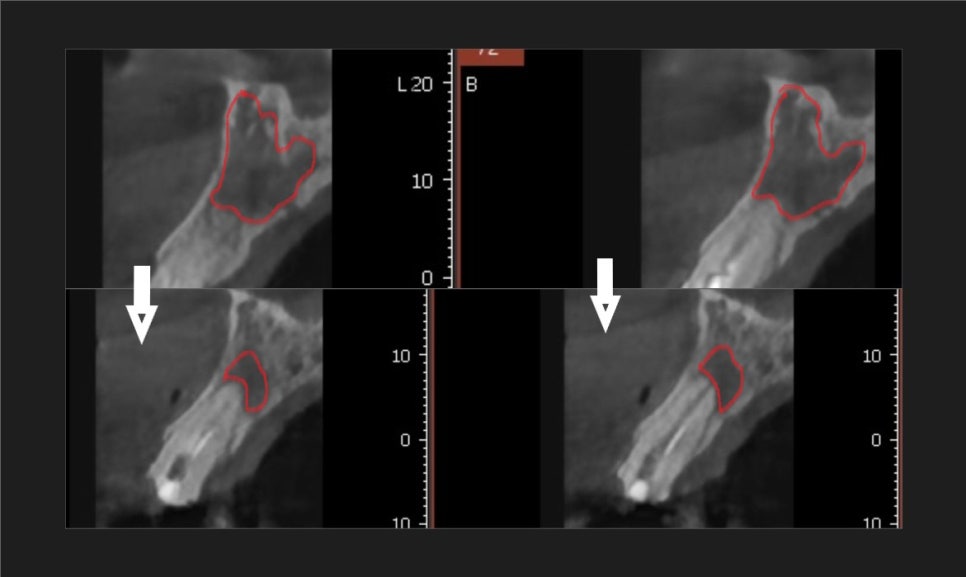

CT 검사 결과를 보니 상태가 꽤 심각했습니다.

왼쪽 앞니(#22) 뿌리 끝 염증이 너무 커져서

주변 잇몸뼈를 대부분 녹여버린 상태였거든요.

사진 속에서 유독 까맣게

빈 공간처럼 보이는 부분이 혹시 보이시나요?

231129

바로 그 부분이 염증이 깊게 자리 잡아

뼈가 녹은 건데요~

이 염증 주머니가 옆 치아(#23)의 뼈까지

침범하며 녹이고 있는 상태였어요.ㅜㅜ

치아가 심하게 흔들리지는 않았지만,

염증의 크기만 봐서는

발치 후 임플란트를 권유받기

딱 좋은 케이스였습니다.

231129 (전) 240215 (후)

놀랍게도 구멍이 뻥 뚫린 것처럼 보였던

염증 부위가

이제는 거의 회복되어 뼈가 단단하게

차오른 것을 확인할 수 있었습니다.